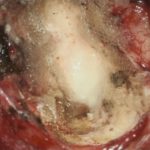

頭蓋内腫瘍摘出術

No.’25_103 摘出 後